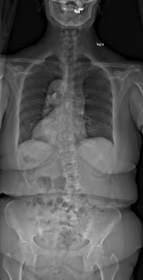

思春期特発性側弯症が高度に進行した症例です。最大側弯角度は113°であり、100°を超える側弯の手術は一般的に神経合併症が危惧されます。神経合併症を極力防ぐため、また侵襲を低減する目的で、同じ入院期間に2回に分けて段階的に矯正手術を行いました。1回目に最も側弯の強い箇所に対して側方から椎体間解離を行い、2回目に後方から全体のバランスが良くなるように慎重に矯正固定術を施行しています。

神経合併症はなく、術後の最大側弯角度は15°に改善(矯正率:87%)、背中の大きなコブも無くなっているのが分かります(赤矢印)。神経合併症が発生しないように慎重に手術を行うのは当然ですが、側弯を治すだけでなく横から見た姿勢を治すことにも留意しています。